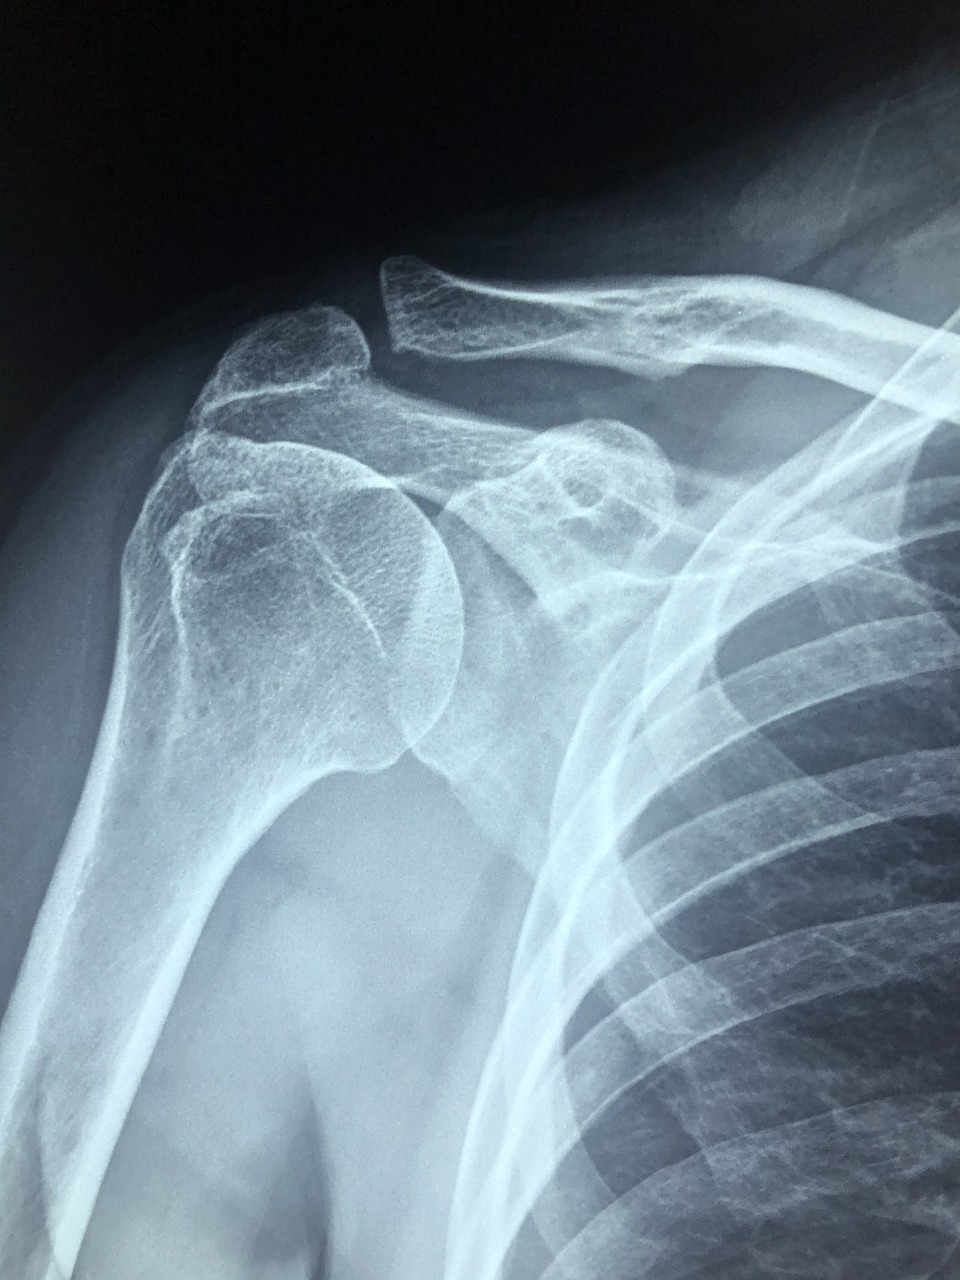

어깨 관절의 구조는 우선 등 쪽에 날개처럼 붙어있어서 날개뼈라고도 부리는 견갑골, 위팔뼈라고도 말하는 상완골, 그리고 빗장뼈라고도 부르는 쇄골로 이루어져 있습니다. 어깨관절은 상완골과 오목한 그릇 형태인 견갑골의 관절와가 만나는 부분을 말합니다. 이 두 뼈의 접촉면은 연골로 감싸져 있어서 마찰 및 충격으로 인한 손상을 막아줍니다. 또한 주변의 관절낭 및 인대들이 서로 연결되어 어깨 관절을 빠지지 않도록 도와줍니다.

정상일 때의 관절낭은 얇고 넓게 관절을 싸고 있는데, 관절낭에 염증이 생기는 병적인 상태에서는 관절낭이 두꺼워지고 힘줄이나 인대와 유착됩니다. 이처럼 어깨 관절을 둘러싼 관절낭 등에 노화 등의 원인으로 발생한 염증이 통증을 일으키고 관절을 굳게 하는 것이 동결견입니다. 그리고 어깨는 '회전근개'라고 하는 4개의 근육이 감싸고 있습니다. 이 회전근개 덕분에 어깨는 우리 몸에서 유일하게 360도 회전을 할 수 있습니다. 이 회전근개 중에 하나라도 손상되면 어깨의 안정성과 근력 전달에 문제가 생깁니다.